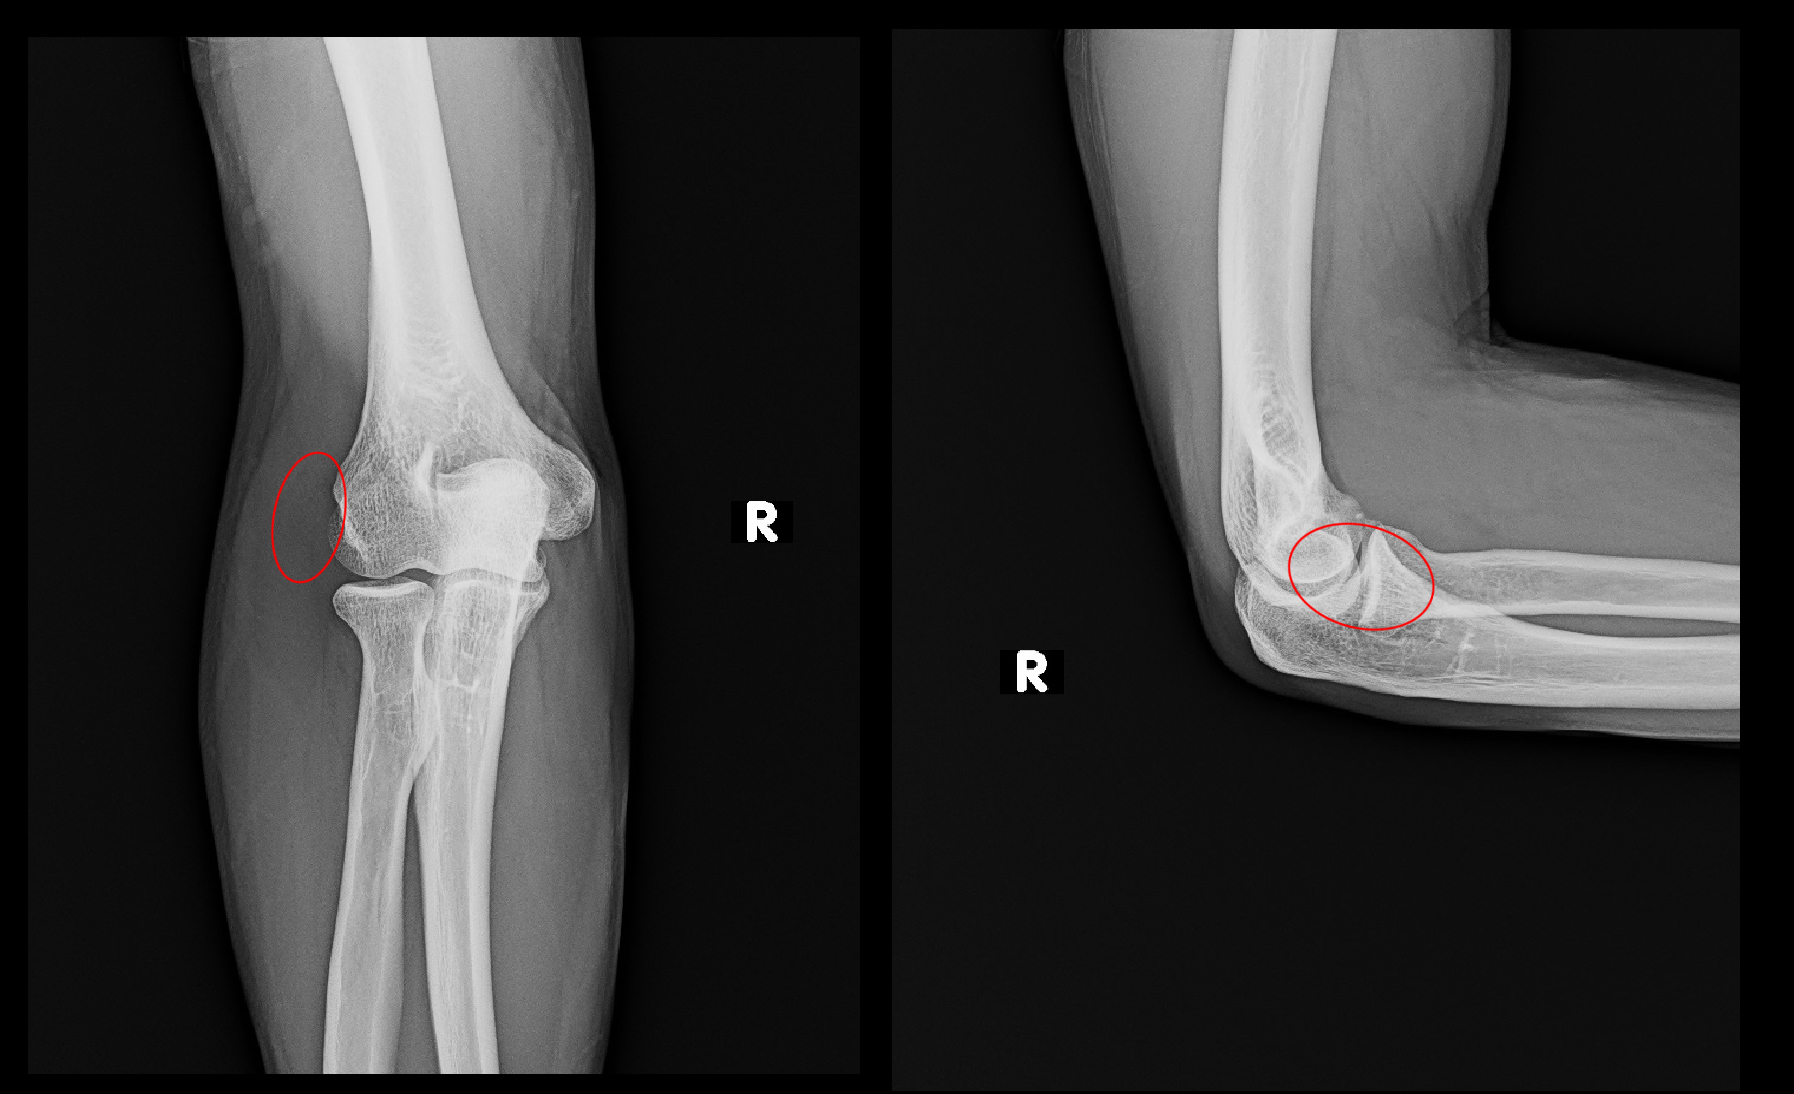

40才の男性です。レントゲンの赤丸領域に痛みを訴えた外側上顆炎の患者さんですが、令和5年の4月と9月に局注の治療を行い、治癒しています。同時期、手指の腱鞘炎の治療も行っていました。

40才男 局注治癒例.jpg令和7年10月に対側である左の外側上顆炎の痛みで受診されましたが、2年前の腱鞘炎の治療は覚えていたのですが、右の外側上顆炎の治療を行っていたことは忘れていました。